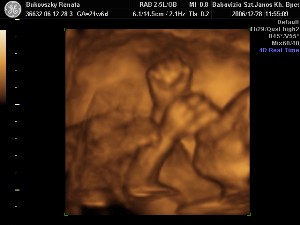

A szülinapom apával és a pocaklakómmal!

A szülinapom apával és a pocaklakómmal!